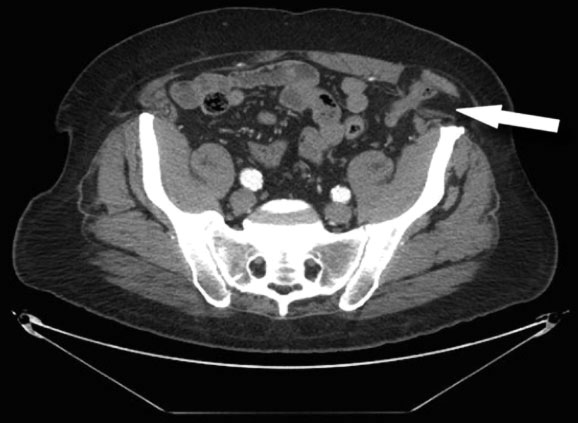

A CT scan of the abdomen and pelvis, however, remains a more useful diagnostic modality.4 This test provides an accurate view of the anterior abdominal wall structures. It is also highly sensitive for detecting intra-abdominal mass lesions in this area.

In Figure 4, notice the colon, marked by the arrow, as it passes through the Spigelian fascia just lateral to the left rectus muscle and becomes entrapped below the external oblique fascia. More inferiorly on the CT scan, in Figure 5, the internal oblique and transversus abdominis muscles can also be seen deep to the hernia, near the iliac crest.